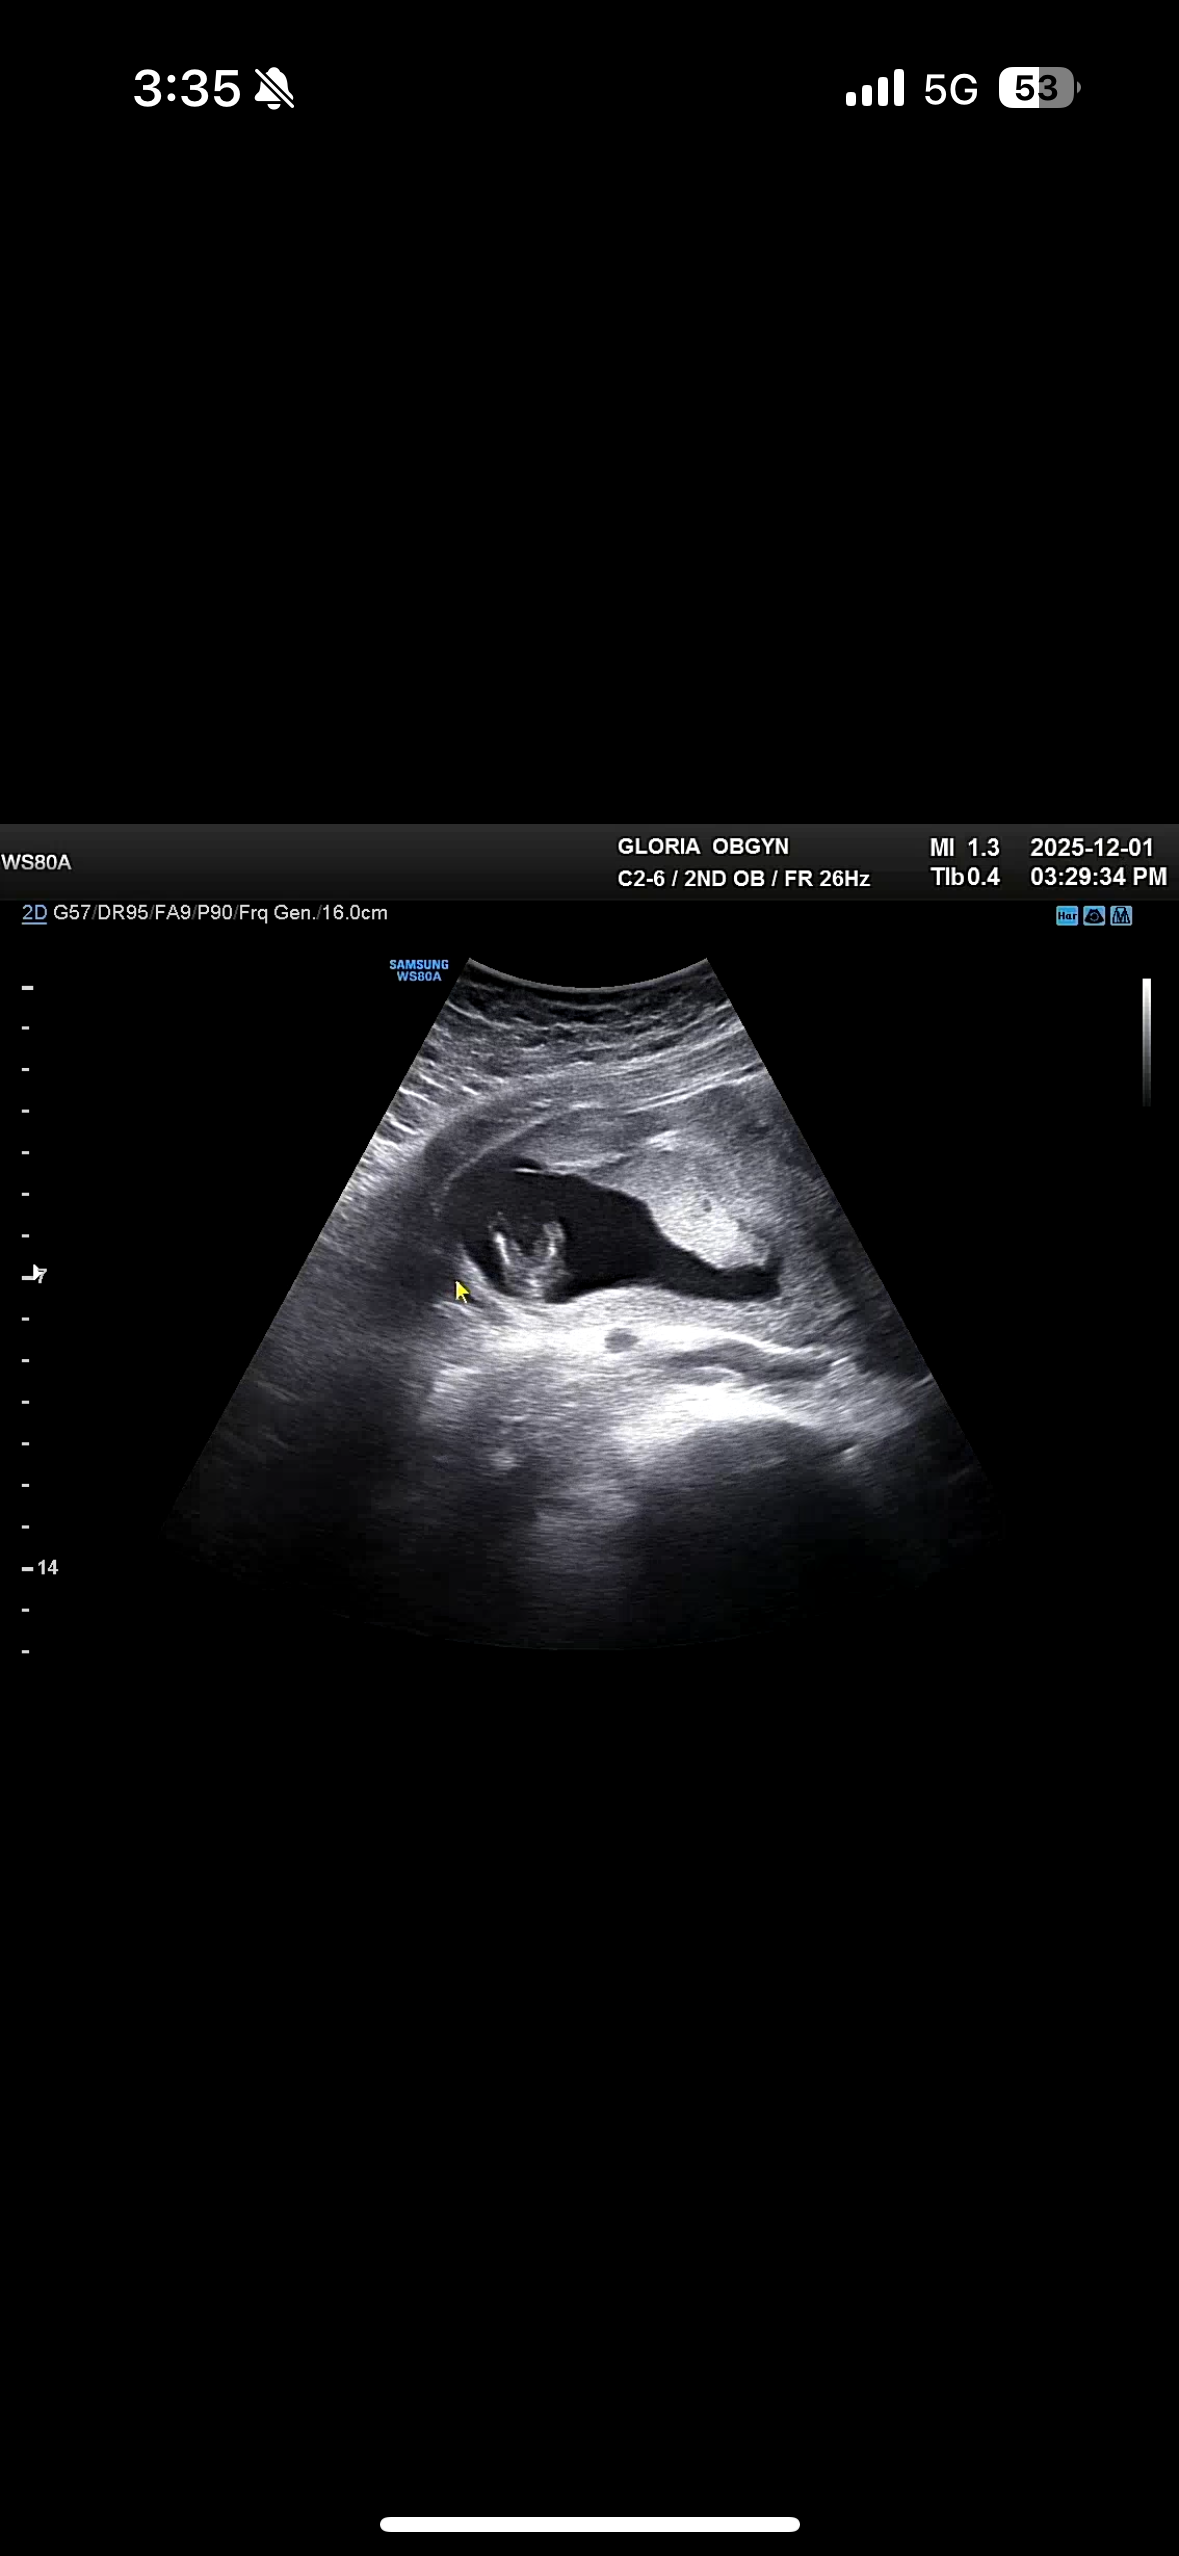

13주 초음파인데 봐주시겠어용 ?

첫째때 11주 부터 아들인걸 알아서요 ㅋㅋ 13주 초음파 다리사이인데 딸같나요??

전 12주에 다리사이에 크게 있던데 ㅎㅎㅎ 요 정도면 딸 아닐까요?